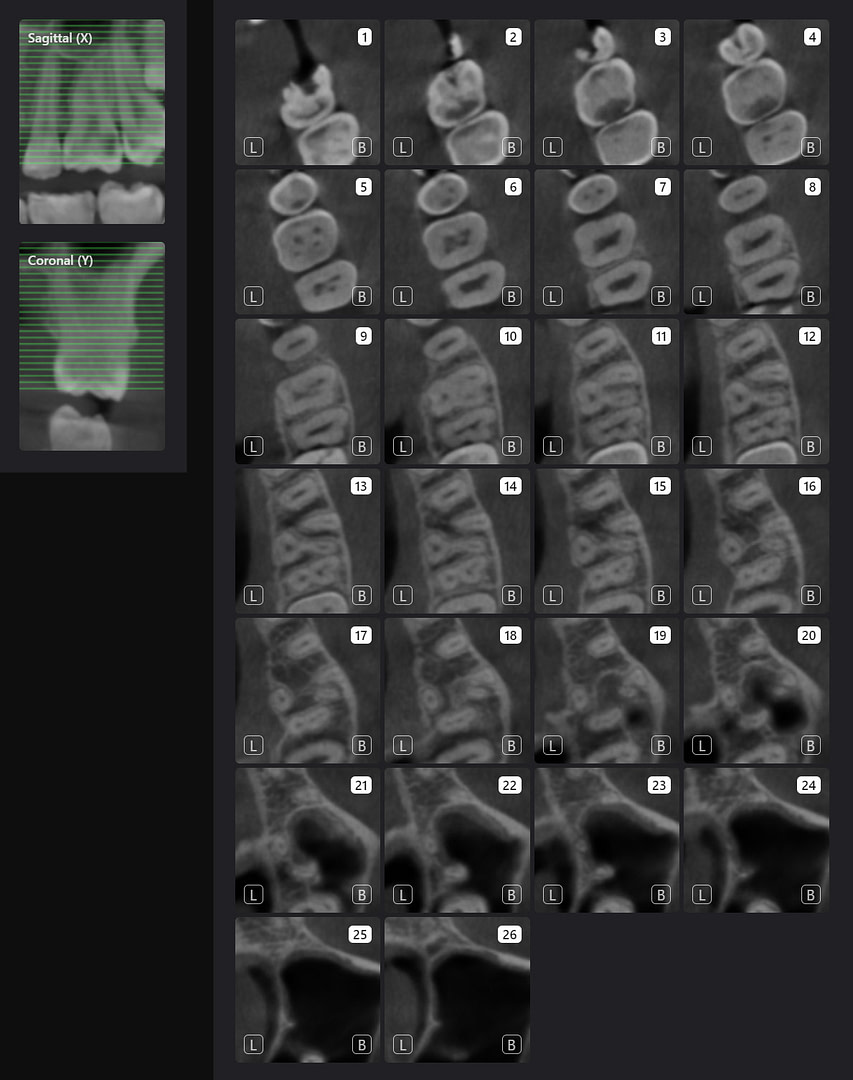

Tooth number is selected to analyze the root canal morphology within the CBCT radiograph.

Sagittal and coronal slices and highlighting the angle/curvature/length of the canals.

Measurement of periapical radiolucency volume is a unique advantage with 3D CBCT versus 2D PA. These are endodontic reports for tooth 12 which had a very large periapical radiolucency. The reports were done before and after a long-term calcium hydroxide dressing.